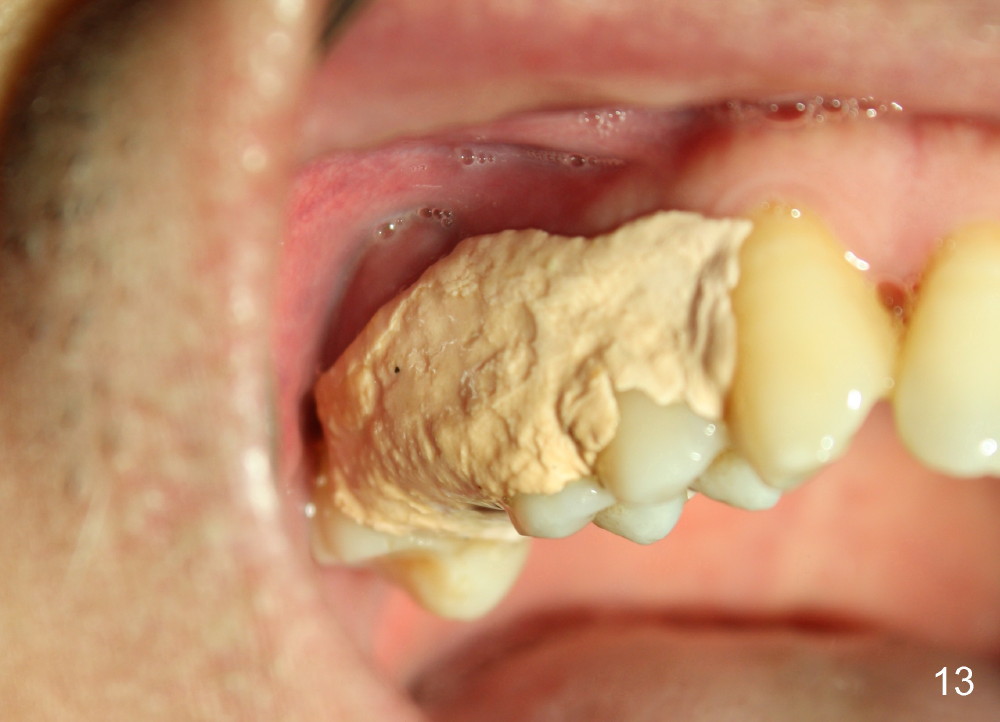

The upper right 1st molar of a 48-year-old man has severe perio endo disease (Fig.1 #3); the bone height for immediate implant (Fig.2) is about 3.5 mm (Fig.1 vertical line). There is a buccal (Fig.3 B) abscess (*); the palatal (Fig.4 P) root is exposed. After extraction, the socket available for immediate implant (Fig.5,6 S) is buccal (without septum), whereas the apex of the palatal root is far away from the main socket. In fact there is an advantage: the socket is smaller. Osteotomy is created in the main socket as palatal as possible, using osteotomes, reamers and taps (Fig.7 T). The sinus floor is lifted (Fig.7 ^). When 7x17 mm implant is placed (Fig.8 I), the insertion torque is >60 Ncm. The remaining socket (Fig.8 *) is to be packed with mixture of autogenous bone, allograft and synthetic bone (Osteogen) (Fig.9,10 <). Immediate insertion of an abutment (Fig.8-10 A) helps retain perio dressing (Fig.11,12). No collagen membrane is used in this case to cover the bone graft before placement of perio dressing. Postop the patient cannot tolerate oral Amoxicillin because of stomach upset. The dose is reduced. Two weeks postop, the perio dressing is stable, but discolors (Fig.13). When the dressing is removed, the buccal bone graft is exposed, which is not abnormal. What is unusual is discoloration (Fig.14). The significance of the latter is not revealed until 3 months postop when the patient remains asymptomatic, but there is an apical fistula (Fig.15 <). There is a communication between the fistula and the buccal sulcus of the implant: water passing freely. Based on the position of the buccal plate of the neighboring teeth (*), the buccal plate of the implant should be lost, which is consistent with finding of PA (Fig.16, as compared to Fig.8). Guided bone regeneration seems necessary.